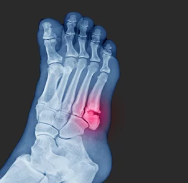

1. 발가락 골절이란? 골절의 종류와 원인

발가락 골절은 발가락 뼈가 충격을 받아 부러지거나 금이 가는 상태를 말합니다. 발가락은 생각보다 작고 약한 구조를 가지고 있어 부상이 잦으며, 골절의 정도와 위치에 따라 치료와 회복 시간이 달라집니다.

발가락 골절의 종류

- 단순 골절: 뼈에 가벼운 금이 가거나 뼈가 부분적으로 부러진 상태로, 비교적 치료가 간단한 경우입니다.

- 복합 골절: 뼈가 여러 조각으로 나뉘거나, 뼈가 관절 밖으로 튀어나온 경우로, 복합적인 치료가 필요할 수 있습니다.

발가락 골절이 발생하면 즉시 통증이 나타나고 붓기나 멍이 들 수 있으며, 발가락을 움직이는 데 어려움을 겪을 수 있습니다.